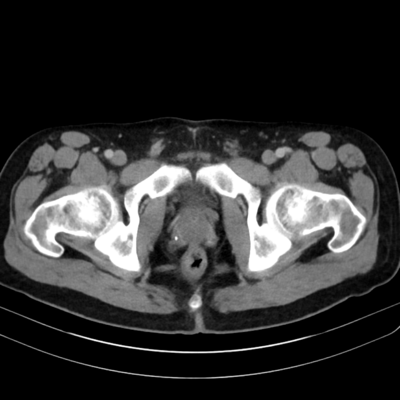

20-30M with recent infection and right pelvic pain. Post your answer!

#bodyrad #RadRes #radiology #FOAMed #genitourinary